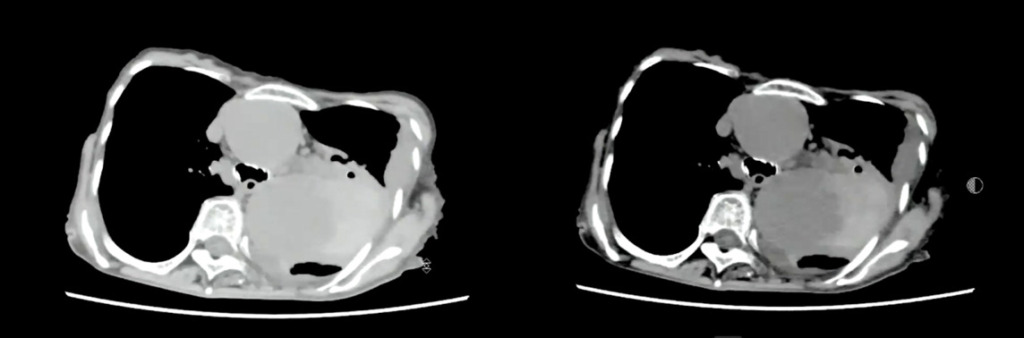

紹介先にて造影CTを施行。

転院先で造影検査を行い、胸部大動脈破裂と大動脈解離StanfordBの診断となっています。

胸部大動脈の著明な拡張と、その周囲に高吸収域を認める(大動脈破裂、contained ruptureを示唆)。